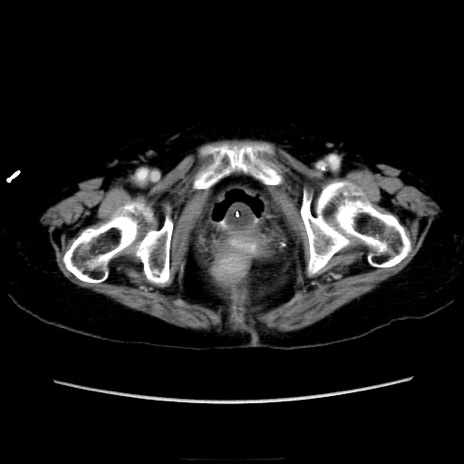

症例40(横断像)

横断像